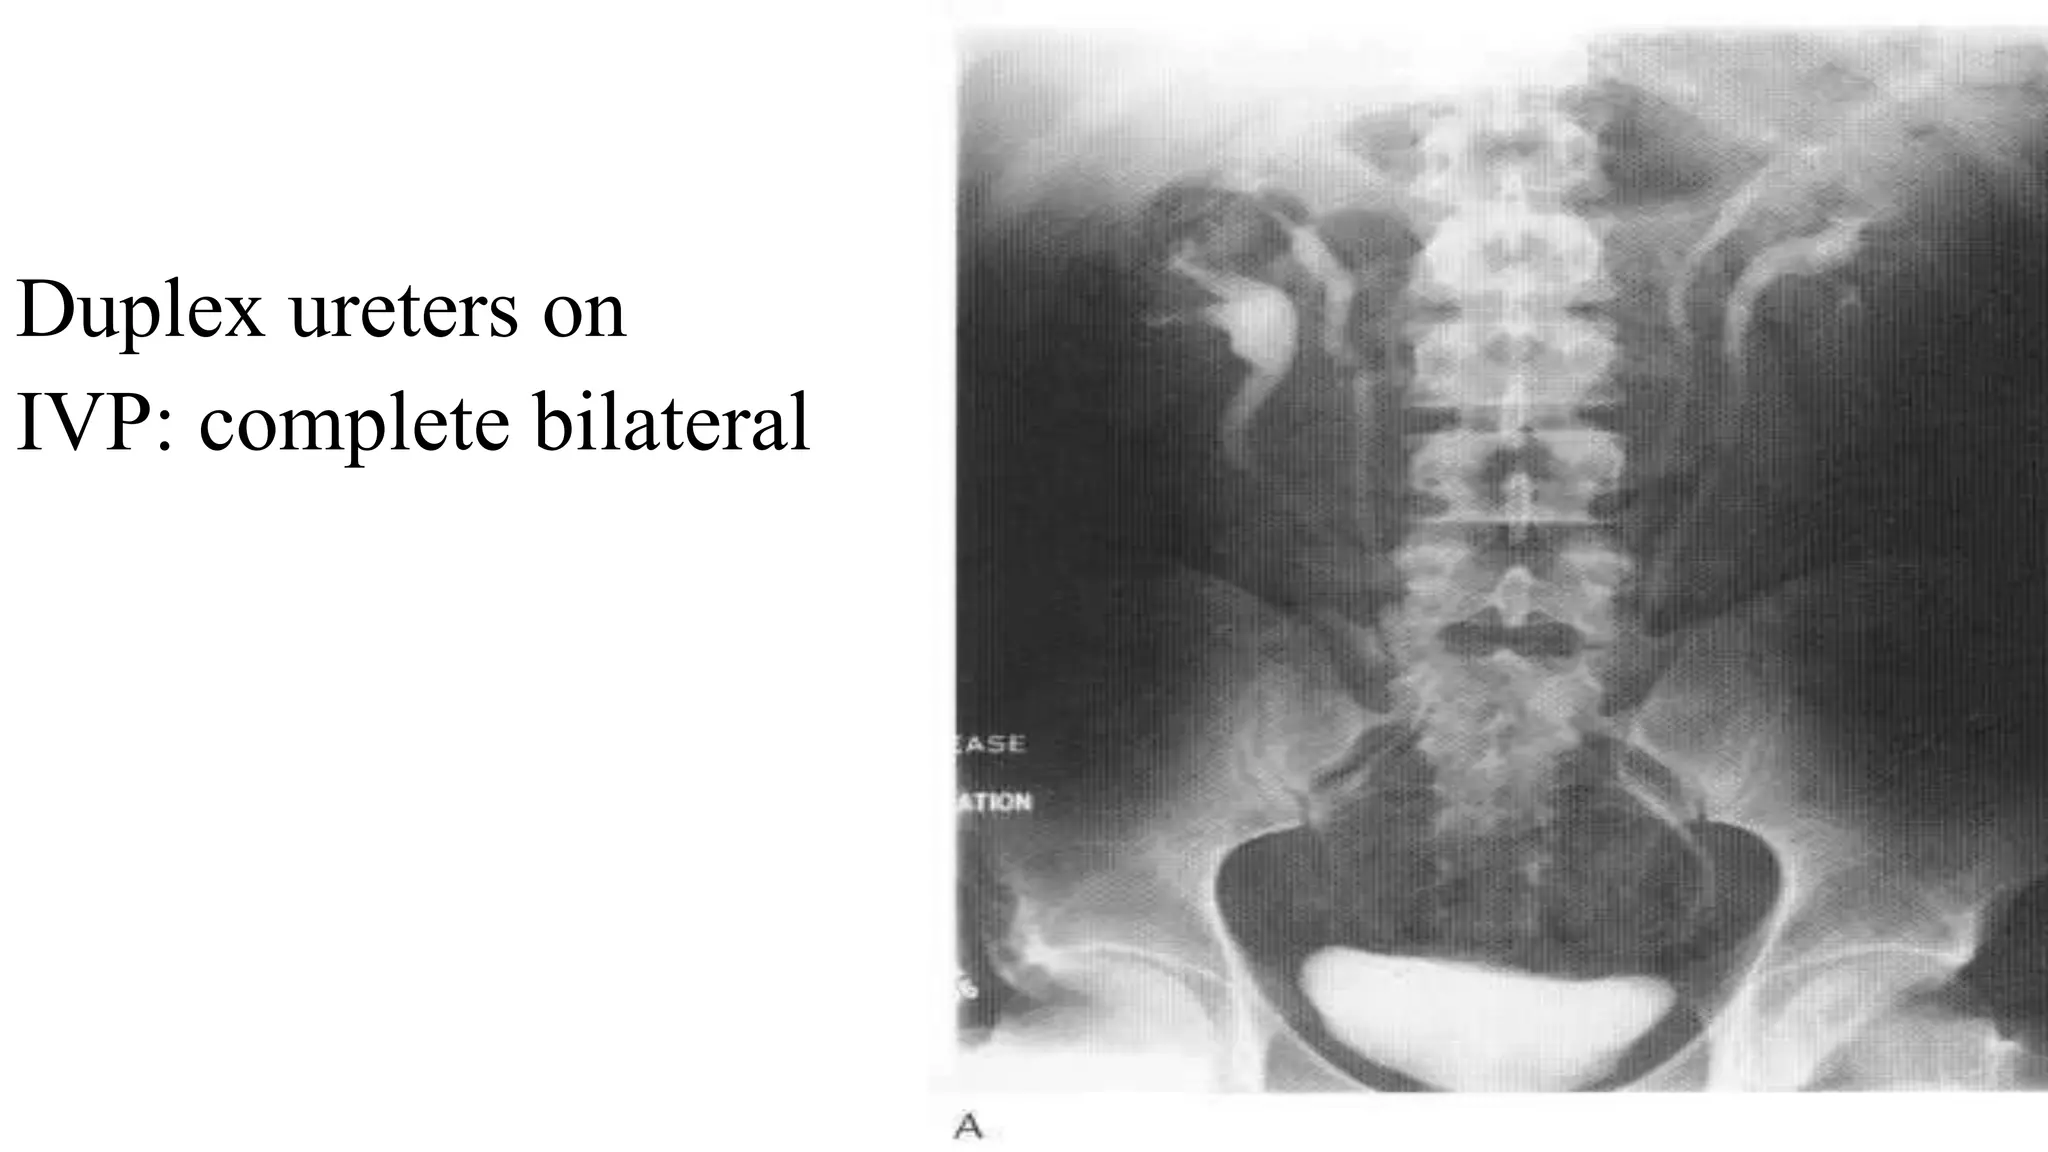

Duplex ureters on

IVP: complete bilateral

Duplex ureters on IVP:complete bilateral